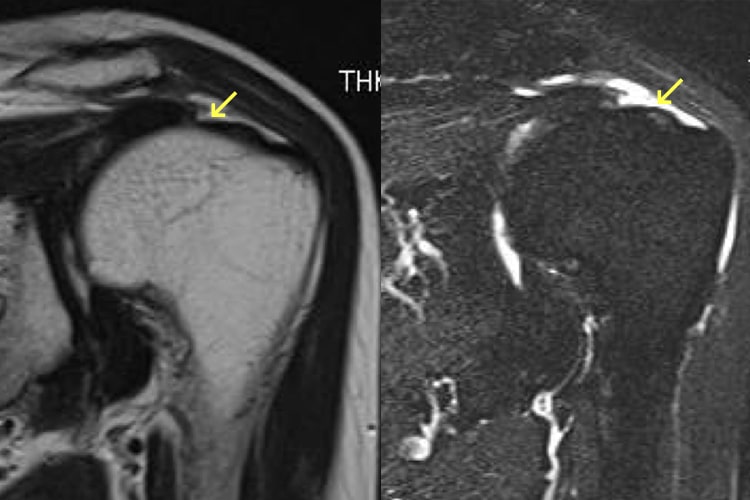

肩腱板断裂

40歳以上の男性に好発し、発症年齢のピークは60代です。肩の運動障害・運動痛・夜間痛を訴えますが、夜間痛で睡眠がとれないことが受診する一番の理由です。運動痛はありますが、多くの患者さんは肩の挙上は可能です。肩関節周囲炎と違うところは、拘縮、すなわち関節が固くなることが少ないことです。 他には、挙上するときに力が入らない、挙上するときに肩の前上面でジョリジョリという軋轢音がするという訴えもあります。急性外傷で始まった時には、三角巾で1~2週安静にします。断裂部が治癒することはありませんが、70%は保存療法で軽快します。保存療法では、注射療法と運動療法が行なわれます。注射療法は、肩関節周囲炎を併発して夜間痛がある場合、ステロイド剤と局所麻酔剤を肩峰下滑液包内に注射し、夜間痛がなくなればヒアルロン酸の注射を行います。腱板の全てが断裂することは少ないので、残っている腱板の機能を高める腱板機能訓練は有効です。こうした保存療法でも肩関節痛と運動障害が治らないときは手術を行ないます。